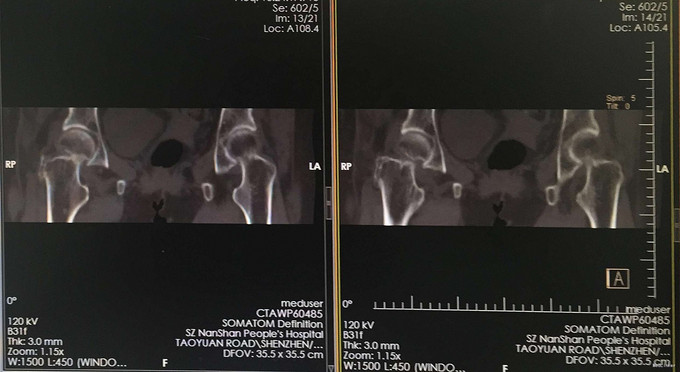

体温37.1℃ 脉搏:79次/分 R:20次/分 舒张压:119mmHg 收缩压:86mmHg。 神清合作,应答切题、全身皮肤黏膜无黄染、浅表淋巴结无肿大,头颅五官无畸形,双侧瞳孔等大等圆,对光反射灵敏。颈软,胸廓对称,双肺呼吸清音,无干湿性罗音。心率79次/分,律齐有力,各瓣膜区无病理性杂音。腹部无异常体征,脊柱盆腔无畸形,双上肢及右下肢检查感觉及活动正常,左下肢检查见专科情况,肛门、外生殖器未检,各生理性反射存在,病理性反射未引出。 专科情况:右髋部无明显肿胀,右下肢呈屈髋、缩短、外形畸形,右髋关节周围广泛压痛,大转子叩击痛,右下肢长度稍短,右大转子在Nelaton线之上,右髋、膝关节活动受限,双下肢无水肿,末梢血运及感觉正常。 辅助检查:我院急诊骨盆正位片: 1、右骨大节骨折可疑,建议进一步检查。 2、右坐骨骨岛:双髋关节螺旋CT平扫+三维重建: a、右股颈骨骨折 b、考虑右髋臼下方髋骨内骨岛。

诊断:右股骨颈骨折 治疗:全髋关节置换术